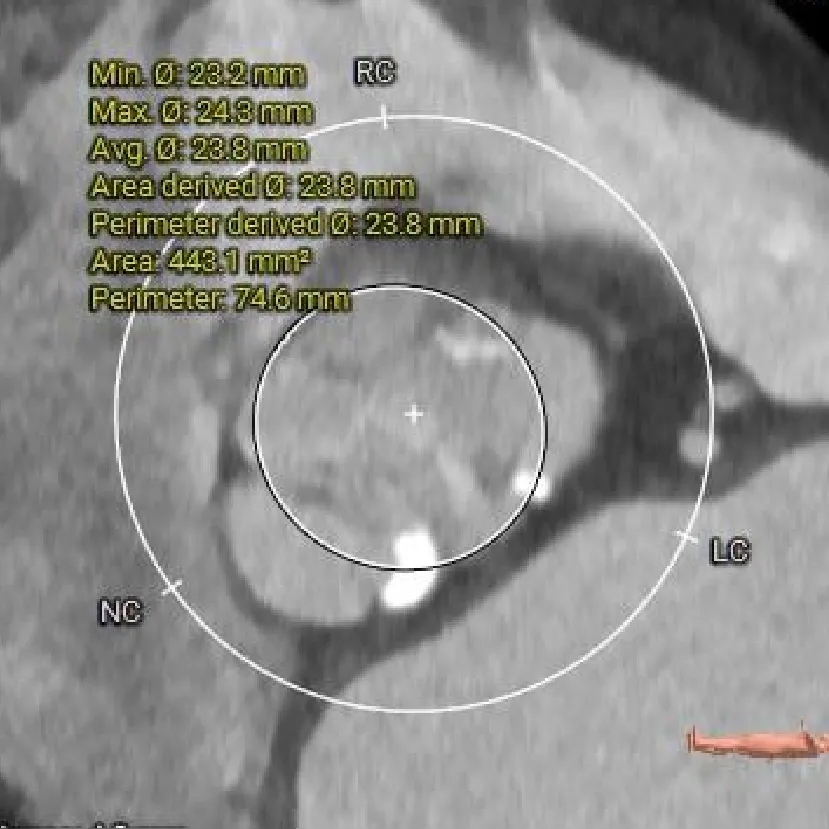

瓣上4mm

23.8mm